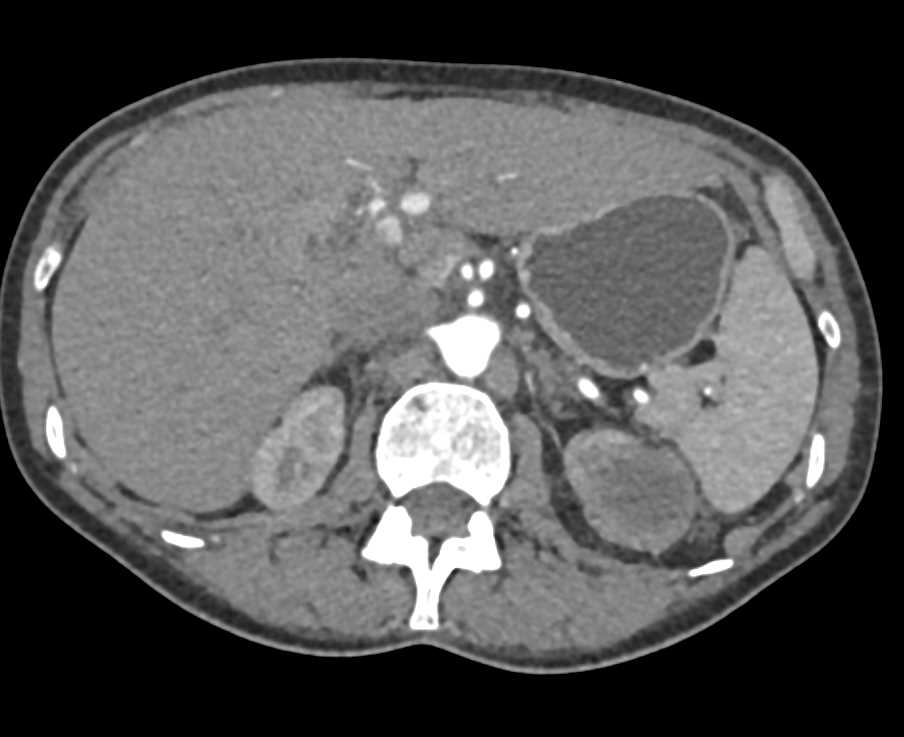

High Density Right Renal Cyst